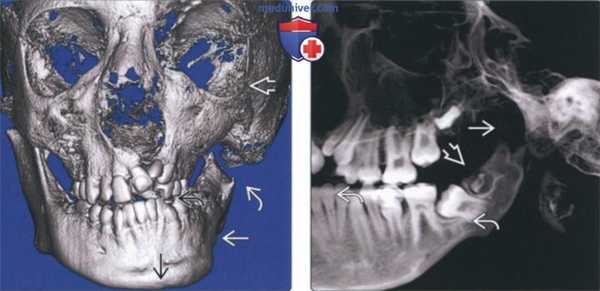

(Слева) На панорамной реформатированной КЛКТ нижней челюсти справа у пациента с левосторонней гипоплазией мыщелка визуализируется небольшой, но в остальном ничем не измененный мыщелок. Нижняя челюсть справа не изменена.

(Справа) На панорамной реформатированной КЛКТ нижней челюсти слева у этого же пациента визуализируется маленький мыщелок, в остальном имеющий нормальную форму. Обратите внимание на уменьшение нижней челюсти, укорочение ветви, выраженную вогнутость заднего края ветви, углубление антегониальной вырезки. (Слева) На панорамной реформатированной КЛКТ определяются множественные переломы, в т. ч. перелом шейки правого мыщелка, выглядящего укороченным. Выраженное смещение под углом, открытым кзади, и повышение плотности в данной области свидетельствуют о переломе.

(Справа) На корональной КЛКТ (поперечный срез под углом) определяется подмыщелковый перелом в левом ВНЧС. Размеры мыщелка не изменены, но на фоне перелома со смещением отломков создается впечатление о его уменьшении. (Слева) На панорамной реформатированной КЛКТ определяется перелом правого мыщелка со снижением его высоты. Шейка мыщелка отсутствует. Такая картина может привести к ошибочному выводу о «маленьком мыщелке», который в действительности представляет собой отломок. Фрагментированный мыщелок смещен кнутри и не виден на данном изображении.

(Справа) На панорамной реформатированной КЛКТ левого ВНЧС определяется импрессионный перелом мыщелка. Мыщелок выглядит маленьким, его шейка укорочена. Переломы такого типа могут приводить к дегенеративным изменениям.